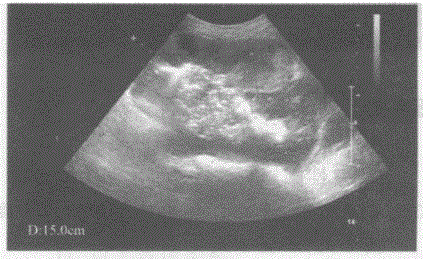

问题 临床资料:女,77岁,自述腹胀、腹痛2月余,加重排便困难、大便变形2周。 临床物理检查:左下腹可扪及一肿物,质硬无活动,轻度压痛。 超声综合描述:左下腹部可见15.0cm×8.0cm×15.0cm假肾样混合性回声区,边界清晰,壁厚1.7cm,中部可见气体样强回声。 超声提示:

选项 A.局限性小肠壁增厚 B.小肠壁增厚肠道实性占位(小肠间质瘤) C.放射性肠炎 D.肠结核

答案 B